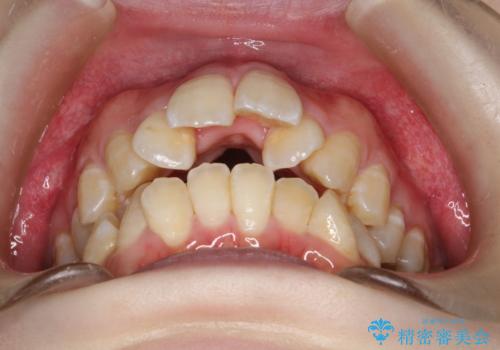

重度のガタガタ ワイヤーによる抜歯矯正

- 出っ歯と全体的ながたつきを主訴に来院されました。

上下の歯に重度のガタガタがあり、前歯が下の歯と咬んでいない状態でした。

審美装置を用いた、抜歯矯正を行うこととしました。